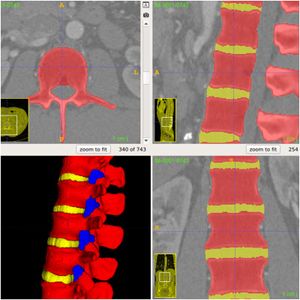

Patient-specific Interactive Software Module for Virtual Preoperative Planning and Visualization of Pedicle Screw Entry Point and Trajectories in Spine Surgery

Publication: Neurol India. 2018 Nov-Dec;66(6):1766-70. PMID: 30504578 | PDF Authors: Muralidharan V, Swaminathan G, Devadhas D, Joseph BV. Institution: Department of Neurological Sciences, Christian Medical College, Vellore, Tamil Nadu, India. Abstract: BACKGROUND: Lumbar pedicle screw insertion involves a steep learning curve for novice spine surgeons and requires image guidance or navigation. Small volume centers may be handicapped by the lack of cost-effective user-friendly tools for preoperative planning, guidance, and decision making. OBJECTIVE: We describe a patient-specific interactive software module, pedicle screw simulator (PSS), for virtual preoperative planning to determine the entry point and visualize the trajectories of pedicle screws. MATERIALS AND METHODS: The PSS was coded in Python for use in an open source image processing software, 3D Slicer. Preoperative computed tomography (CT) data of each subject was loaded into this module. The entry-target (ET) mode calculates the ideal angle from the entry point through the widest section of the pedicle to the desired target in the vertebral body. The entry-angle (EA) mode projects the screw trajectory from the desired entry point at a desired angle. The performance of this software was tested using CT data from four subjects. RESULTS: PSS provided a quantitative and qualitative feedback preoperatively to the surgeon about the entry point and trajectories of pedicle screws. It also enabled the surgeons to visualize and predict the pedicle breach with various trajectories. CONCLUSION: This interactive software module aids in understanding and correcting the orientation of each vertebra in three-dimensions, to identify the ideal entry points, angles of insertion and trajectories for pedicle screw insertion to suit the local anatomy. |

EA mode of pedicle screw trajectory planning in a patient with high grade L5-S1 spondylolisthesis. (a) Correction of vertebra rotation. (b) Marking of fiducials. (c) Desired trajectory for selected entry point and angle. (d) Marking of the entry and target fiducials for desired iliac wing screw. (e) Ideal trajectory of iliac wing screw and panel displaying the angle of screw trajectory using entry-target mode. |